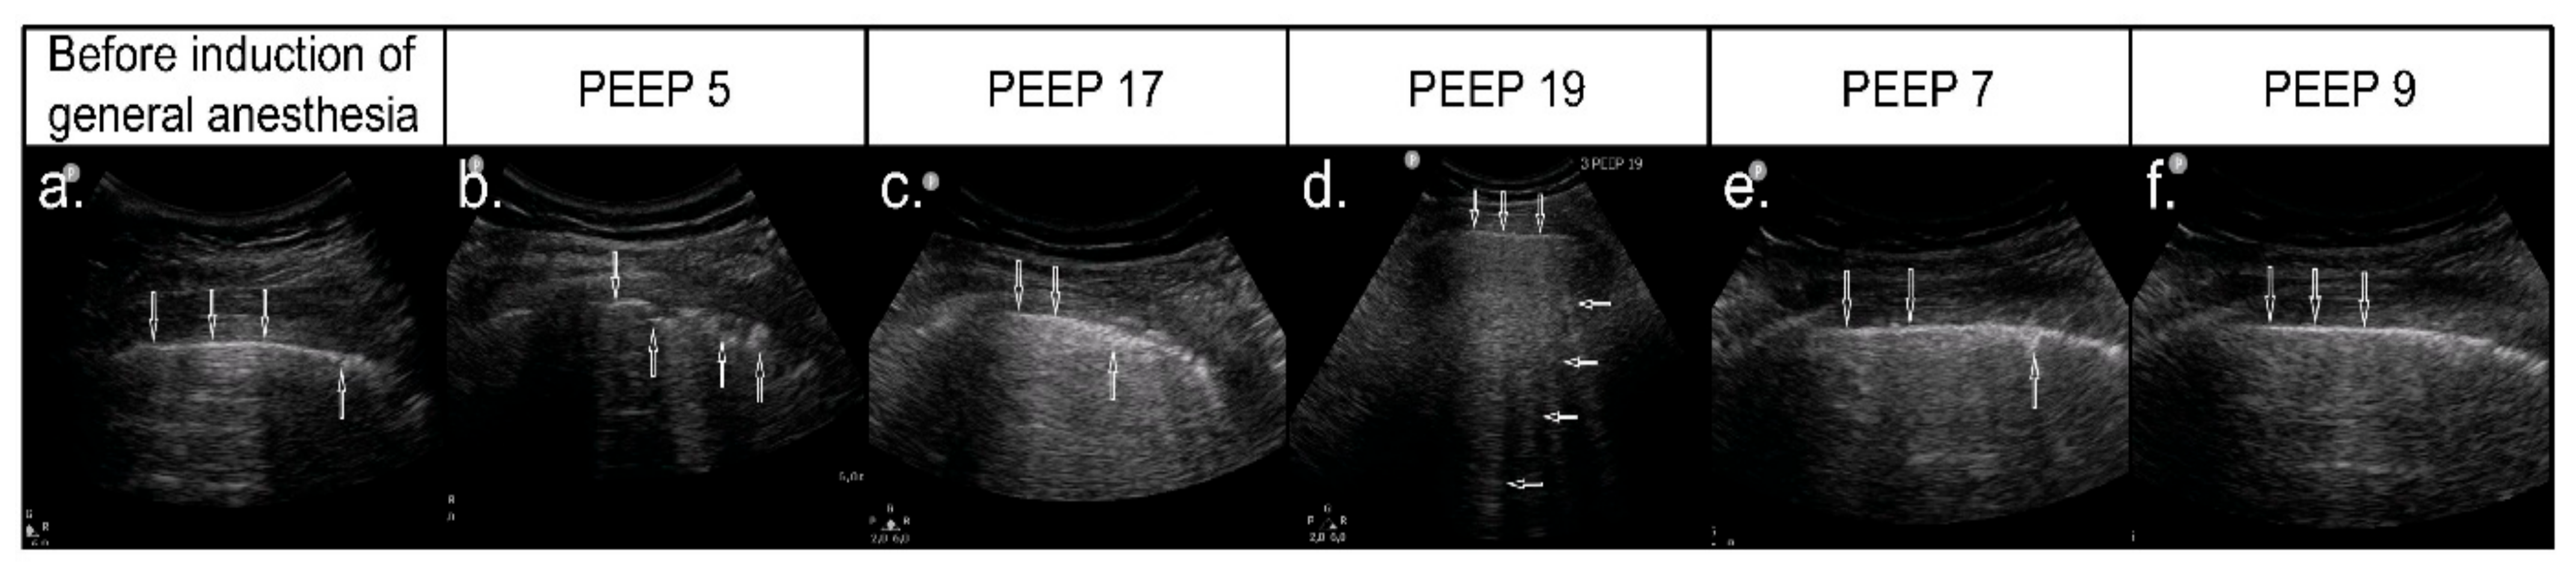

3.4. Effect of Ultrasound-Guided Recruitment Maneuver